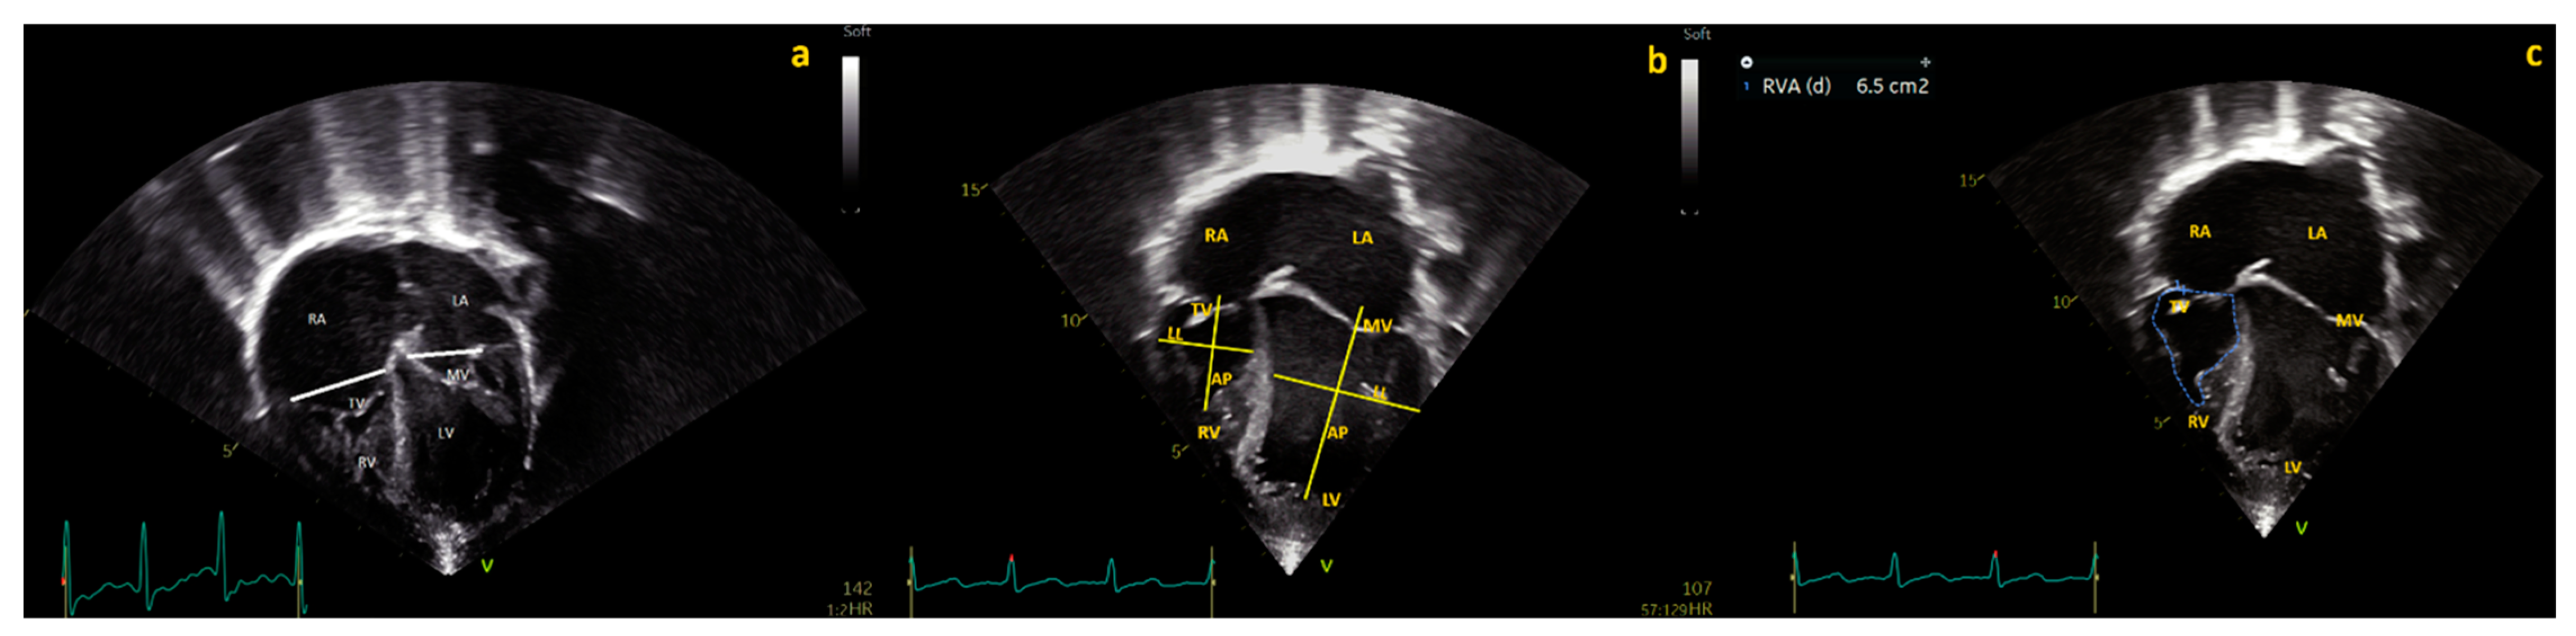

Figure 2.

Four chamber view of a PAIVS with diminutive, hypertrophied RV. (a) Mitral valve (MV) and tricuspid valve (TV) diameters. (b) Base–apex and laterolateral diameters of the right (RV) and left ventricles (LV), (c) right ventricle end-diastolic (RVED) area.